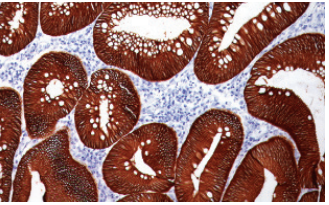

Pepsin digestion was utilized with MOC-31 antibody on colon cancer. Amyloid

P, Cytokeratin 17, and Ber-EP4 are a few other of Biocare’s antibodies that

recommend pepsin digestion.